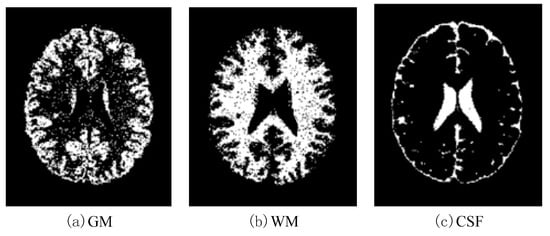

In this paper, we used two types of images. One type of data comes from the Simulated Brain Database (SBD). MRI images can be downloaded from this database. Another kind of image is real an MRI image downloaded from the website of Harvard Medical School. In our experiments, we only retained three main brain tissues, including GM, WM and CSF, but there were skulls and other tissues in the original image.

AANLIB: There are many T2-weighted MRI brain images in the image dataset. The images have higher resolution. Because T2 images have higher contrast and clearer vision than T1 modalities, we choose the T2 model for this type of data set. This dataset of the MRI image of the malignant brain is comprehensive. The sample images of disease are shown in Figure 11.

We selected five images from the dataset randomly, which included 17 types of malignant brain images and a benign brain image. The chosen five images contain four brain diseases and a benign one. That is, we select 5 × ( 1 + 17 ) = 90 images to form a brain MRI image dataset.

Figure 11. Sample of brain MRIs.